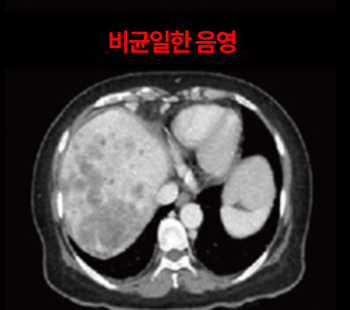

2023.2.2 腹部CT

2025.3.14 腹部CT

伴随肺转移的肝癌 4期 诊断

10日集中 高频热疗 实施